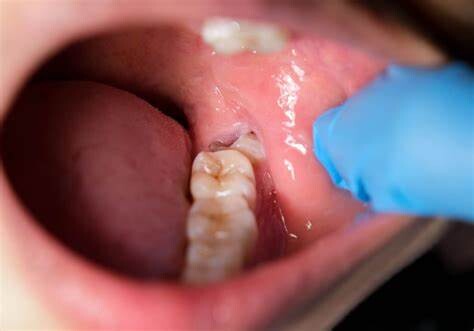

Mutilates the Neighbouring Teeth

Since there is not enough room for the tooth to grow, it will case the teeth to grow in an abnormal manner. This results in impaction of the teeth, giving rise to many other oral problems. When the wisdom tooth emerges against the second set of molar, it might damage them, increasing the risk of acute infection. It will also have an effect on other teeth, which will intensify the need for an orthodontic treatment to align the other teeth.

Tooth Decay

The fully impacted or the partially impacted wisdom teeth are at greater risk of tooth decay, than other teeth. This usually happens, because of the location of the wisdom tooth, especially towards the back of the mouth, which is hard to clean. Moreover, since it lies at the back of the mouth, there are chances of food getting easily trapped between the gums and the tooth, promoting the growth of bacteria.